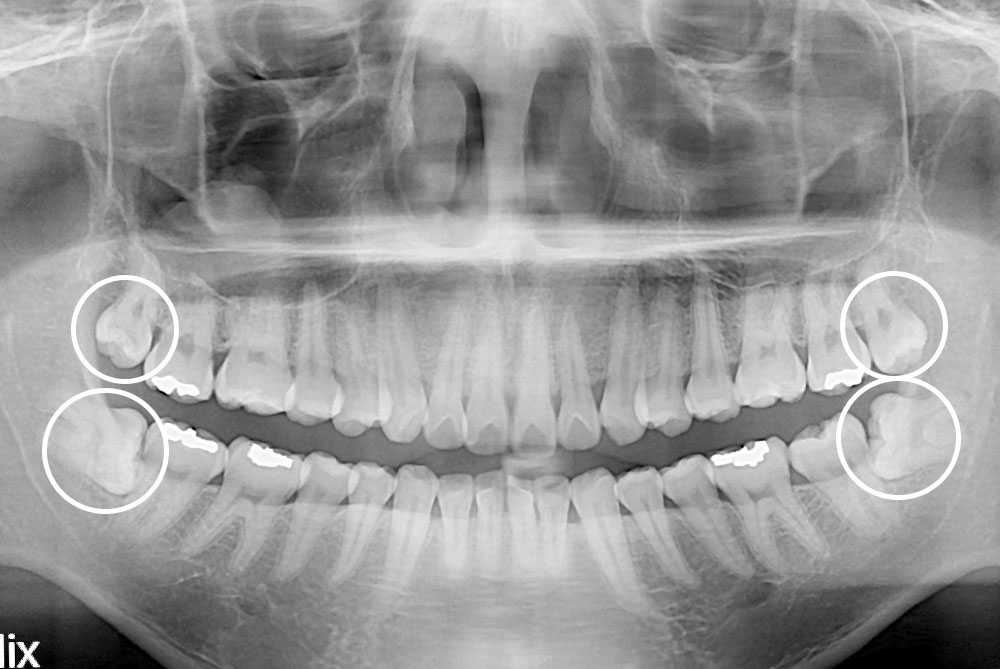

[사랑니] 매복 사랑니 발치

치료전 : 2019-12-03